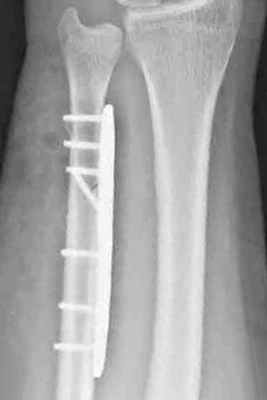

Оперативное лечение диафиза лучевой и/или локтевой кости

Переломы без смещения или с незначительным смещением в этой области достаточно редки, поэтому большинство подобных переломов требует оперативного лечения. Оно заключается в фиксации отломков (остеосинтез). Возможные варианты фиксации - установка пластины на кость или специальных штифтов (стрежней) внутрь кости. Метод выбирается по показаниям – в зависимости от величины отека, смещения отломков и других факторов (возраст, род занятий пациента).

Остеосинтез лучевой/локтевой кости пластиной

После выставления отломков в правильное положение металлическая пластина фиксируется на кости с помощью специальных винтов, не давая отломкам сместиться. Если сломаны и лучевая, и локтевая кость, устанавливается две пластины. После операции на руку накладывается защитная гипсовая лонгета, в среднем – на 2-3 недели. Средний срок госпитализации при подобном оперативном вмешательстве – 7 дней. После выписки необходимо делать перевязки в амбулаторном режиме (в поликлинике). Через 2-3 недели лонгета снимается, и назначается курс восстановительного лечения – лечебная физкультура, физиотерапия. Пластины удаляются в среднем через год.